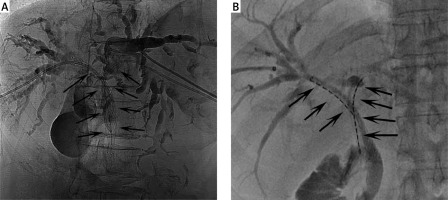

Normal stent insertion

A side-by-side percutaneous approach was used for the insertion of bilateral stents. Following the simultaneous puncture of the left and right intrahepatic biliary tracts, two VER catheters were introduced via a 0.035-inch Radifocus guide wire (Terumo, Tokyo, Japan) to detect the obstruction. After the catheters had reached the obstruction and entered the duodenum, stiff guide wires (Cook, IN, USA) were used to replace the Radifocus guide wires. Two delivery systems were then introduced with the stiff guidewires to the site of the obstruction and simultaneously released in a Y shape (Photo 1 A).

Radioactive stent insertion

A side-by-side percutaneous approach was used for the insertion of bilateral radioactive stents. Briefly, two stiff guidewires were initially introduced, with two additional guidewires being used to pass two 6F sheaths across the obstructed sites. Stents were placed at the center of the obstructed site with a 0.035-inch stiff guidewire. Then, 125I seed strands were placed within 6F sheaths; with these sheaths removed the seed strands were positioned between the stent and the biliary wall. These two stents were positioned in a Y shape (Photo 1 B).